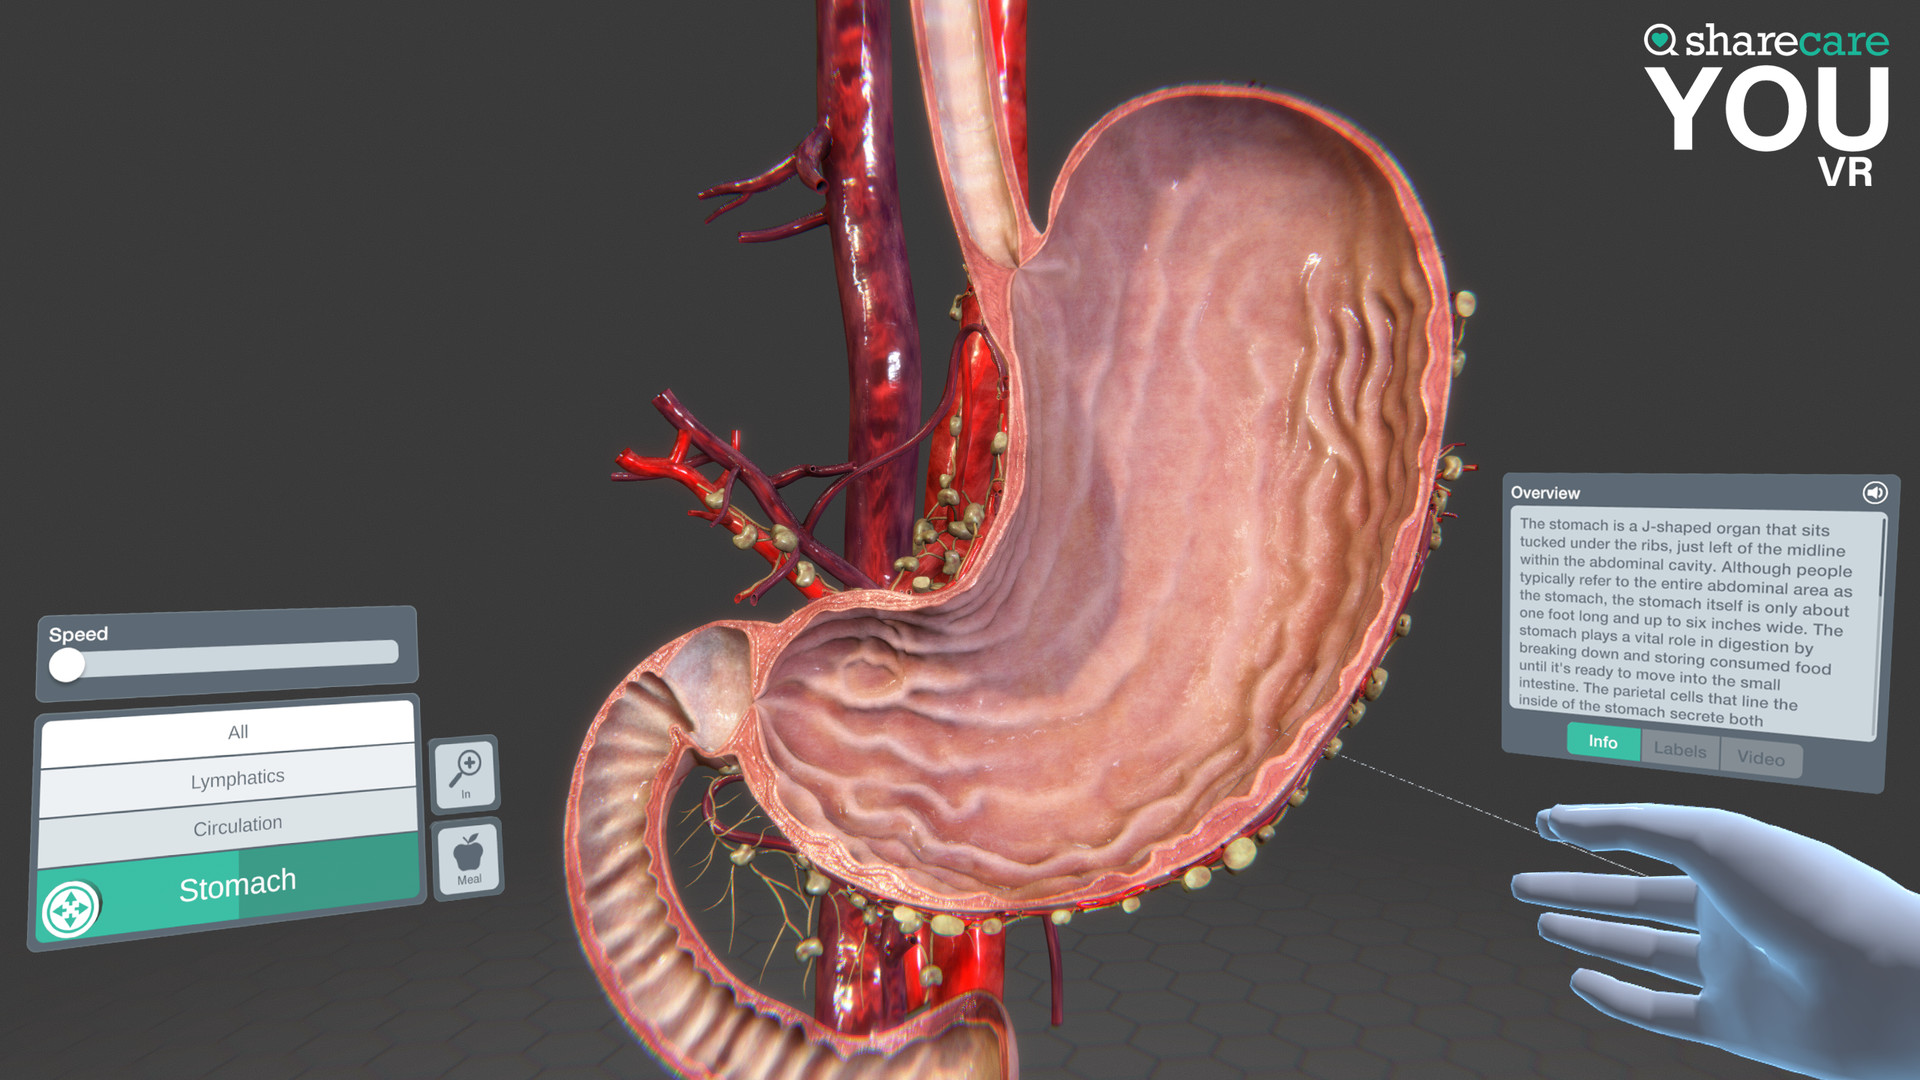

Sharecare YOU是一种完全身临其境的、逼真的人体模拟,让任何人都可以 360 度全方位探索其惊人的细节。

有兴趣了解特定器官吗?只需单击一个按钮,即可进入内部,想象其自然功能,并深入探索。想了解更多吗?查看沿途的许多标签和标签,以获得更多信息和洞察力。轻松定制您以更好地了解生理学和模拟疾病。您甚至可以将我们的头像个性化为虚拟的您——您的健康、您的状况。这真的是关于你的。

- 你的内容 – 一个包含 40 多个不同场景的扩展库供探索,包括解剖学、生理学、条件和治疗

- 信息标签和场景信息

- 具有独特交互式控件的完全更新的用户界面